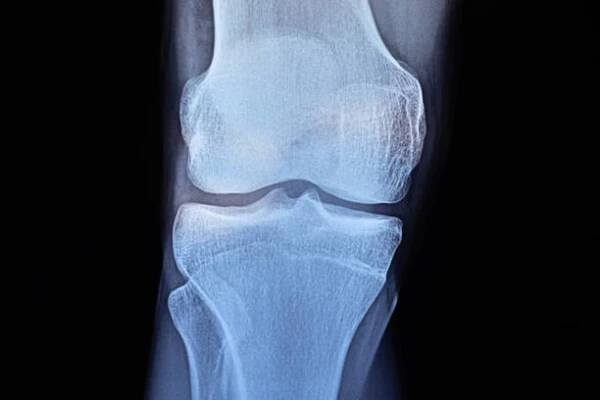

Osteom je benigní (nezhoubný) kostní nádor, který vzniká z kostní tkáně. Osteomy jsou obecně neškodné, rostou pomalu a málokdy se mění v maligní (rakovinné) nádory.

Osteom je nezhoubný nádor, který vychází z kostních buněk (osteocytů). Osteomy jsou sice nezhoubné, ale svým růstem mohou způsobit svému nositeli celou řadu problémů.

Osteom je benigní nádor kostí. Roste pomalu a vyskytuje se jako lokalizovaný novotvar v kostní substanci. Vzniká hlavně v kostech lebky, zejména v nosní dutině. Wikipedie